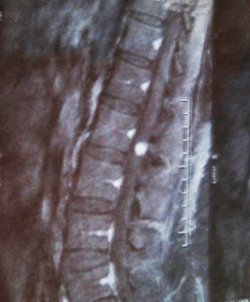

Sitting in the little room with my mom awaiting the x-ray results, it felt surreal. The doctor came back and said there was a spot in my spine in the L1-L3 region and he wanted to order an MRI. The MRI was frightening. They had to inject dye into me so that the tumor would show up. And it did. There it was, the spot that was causing my body such distress. The doctor was 99% sure it was an Schwannoma tumor, which could be easily removed.